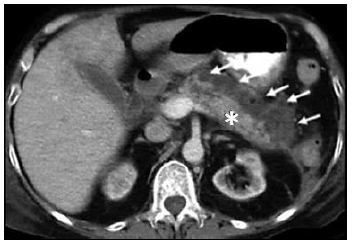

Observe atentamente a seguinte TC abdominal com contraste VOVO e IVIV:

É

correto

afirmar que a imagem anterior trata-se

de necrose pancreática, com as setas demonstrando a área ainda sadia, e o asterisco a área do pâncreas necrosada.

de necrose pancreática, com as setas demonstrando a área de necrose, e o asterisco a área do pâncreas ainda sadio.

de um infarto mesentérico, com as setas demonstrando a área de necrose, e o asterisco a área de omento ainda sadio.